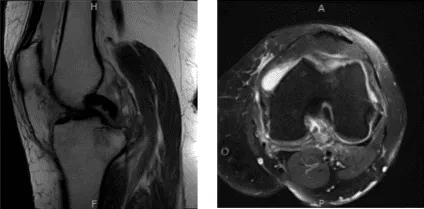

Durante la visita de seguimiento se presentó un resultado de resonancia magnética que mostró osteoartrosis con pérdida de cartílago de alto grado en el compartimento medial y pérdida de cartílago de alto grado cartílago troclear central con pérdida condral de bajo grado cartílago rotuliano.

Se observan cambios quísticos subcondrales y edema en la tibia medial. Esto puede ser secundario a la osteoartritis, aunque no puedo excluir que se desarrolle insuficiencia fractura tibia medial.

Gran desgarro radial del cuerno posterior del menisco medial, que está extruido periféricamente. Bursitis por anserina. Derrame articular de rodilla grande con cuerpo intraarticular flojo.

Resonancia magnética – Rodilla izquierda sin contraste